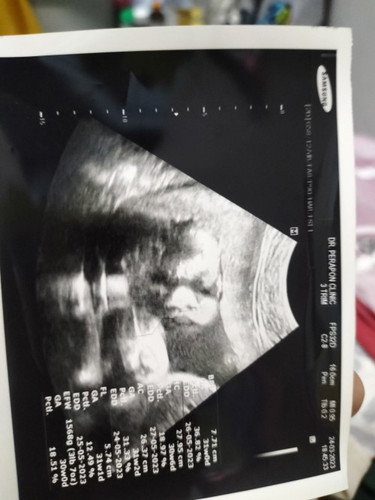

ท้องได้30วีค น้ำหนักลูกน้อยไปไหมคะ

ไปซาวด์มาหมอบอกว่า1568กรัม โลครึ่ง แม่ๆว่าน้ำหนักน้อยไปไหมคะ มีวิธีเพิ่มน้ำหนักลูกไหมคะ#ขอคำแนะนำหน่อยค่ะ #ขอบคุณล่วงหน้านะคะ 🙏🙏